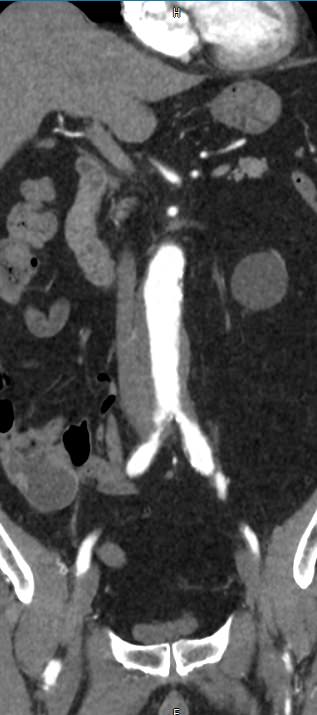

Аорта – это самый крупный кровеносный сосуд в организме человека. Брюшная аорта является продолжением грудного отдела аорты и расположена ниже аортального отверстия диафрагмы. На уровне 4-5 поясничных позвонков находится бифуркация аорты, где она делится на две общие подвздошные артерии, несущие кровь к нижним конечностям.

От брюшной аорты отходит несколько висцеральных ветвей,  кровоснабжающих внутренние органы. К ним относятся: почечные артерии, чревный ствол, который кровоснабжает органы пищеварения, верхняя и нижняя брыжеечные артерии, питающие кишечник, яичковые артерии у мужчин, яичниковые – у женщин.

Мультиспиральная компьютерная томография является лучевым методом исследования и в режиме ангиографии применяется для диагностики сосудистой патологии брюшной аорты и ее ветвей. Сканирование проводится с помощью рентгеновских лучей, которые испускает трубка томографа, непрерывно вращаясь вокруг объекта исследования.

Особенностью КТ-ангиографии является обязательное применение контрастного усиления, которое позволяет визуализировать кровеносные сосуды. С помощью внутривенного введения йодсодержащих контрастных препаратов на снимках хорошо контрастируются висцеральные ветви и сама аорта, участки сужения и расширения сосудов, можно диагностировать атеросклеротические бляшки и тромбы в просвете сосудов.

При помощи цифровых приложений данные, полученные при сканировании, трансформируются в трехмерные изображения сосудистой системы. Это позволяет оценить пространственное соотношение анатомических структур и часто применяется в ходе предоперационной подготовки и для оценки успешности проведенной операции.